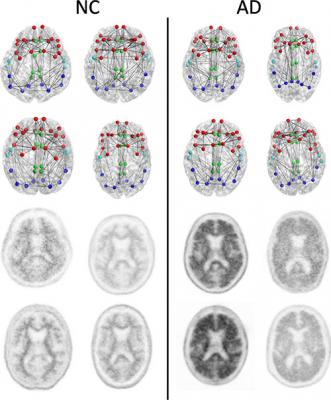

For this study, researchers looked at the brain's structural connectome, a map of white matter tracts that carry signals between different areas of the brain, which provides a way to characterize and measure these connections and how they change through disease or age.

Results from 102 patients enrolled in a national study called the Alzheimer's Disease Neuroimaging Initiative (ADNI) 2 were analyzed. The patients had undergone diffusion tensor imaging (DTI), an MRI method that assesses the integrity of white matter tracts in the brain by measuring how easy it is for water to move along them.

The researchers correlated changes in the structural connectome with results from florbetapir positron emission tomography (PET) imaging, a technique that measures the amount of beta amyloid plaque in the brain. Increased florbetapir uptake corresponds with greater amounts of the protein.

The results showed a strong association between florbetapir uptake and decreases in strength of the structural connectome in each of the five areas of the brain studied.